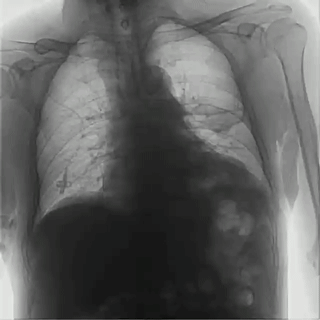

不同于常規(guī)DR只能進(jìn)行平片攝影檢查,普利德多功能動(dòng)態(tài)平板DRF動(dòng)靜兼?zhèn)?,可?shí)現(xiàn)大幅面低劑量透視檢查,在日常的體檢工作中,比如胸部及肺部檢查,可對(duì)重疊部位病變進(jìn)行可視化觀察及多角度旋轉(zhuǎn)體位,發(fā)現(xiàn)疑似病灶可瞬時(shí)完成高清點(diǎn)片,顯著提高診斷的準(zhǔn)確性。

動(dòng)態(tài)采集幀率最高可達(dá)30幀/s,影像細(xì)膩流暢,便于醫(yī)生對(duì)細(xì)微病變的觀察。17×17英寸大幅面成像,在透視過程中能對(duì)患者的胸部腹部等部位實(shí)現(xiàn)大范圍覆蓋,便于從整體上觀察組織信息,更加全面且精準(zhǔn)的捕捉病灶。